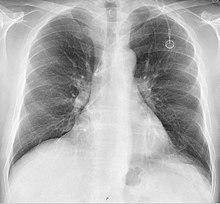

A follow-up chest radiograph can immediately detect complications associated with the procedure in the form of pneumothorax, hemothorax and malpositions of the catheter (see Risks below for further details). However, it is suggested that chest radiography is not mandatory as a routine method after fluoroscopy-guided port insertion that is mainly performed by venous cutdown.[3]